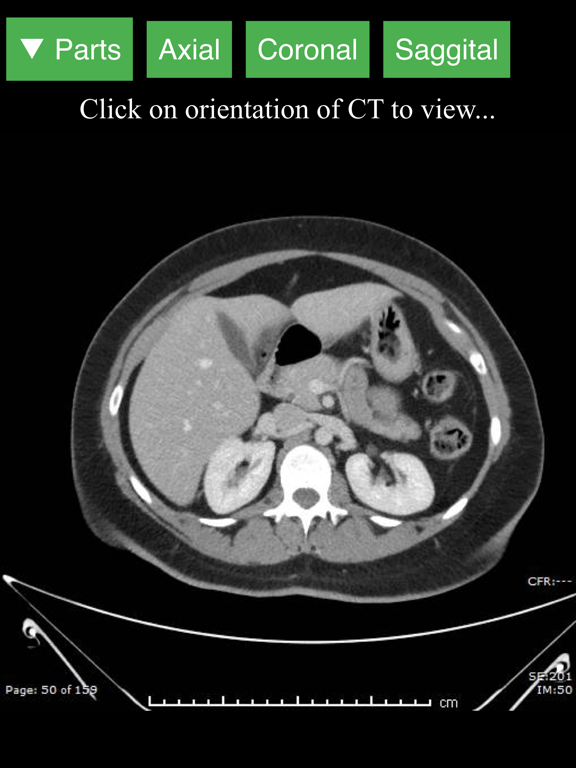

CT Abdomen Pelvis

Lieu Duong

| 9 | CT Abdomen Pelvis | 3.00 | 2.7 ⭐ |

CT Abdomen Pelvis

MD Toolkit

| 7 | CT Abdomen Pelvis | 120K | 2.9 ⭐ |